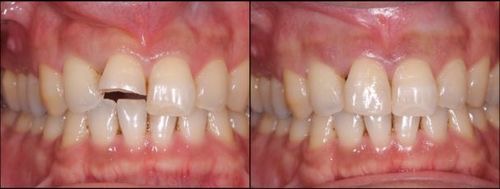

ダイレクトボンディングにより

右上1番を修復した症例